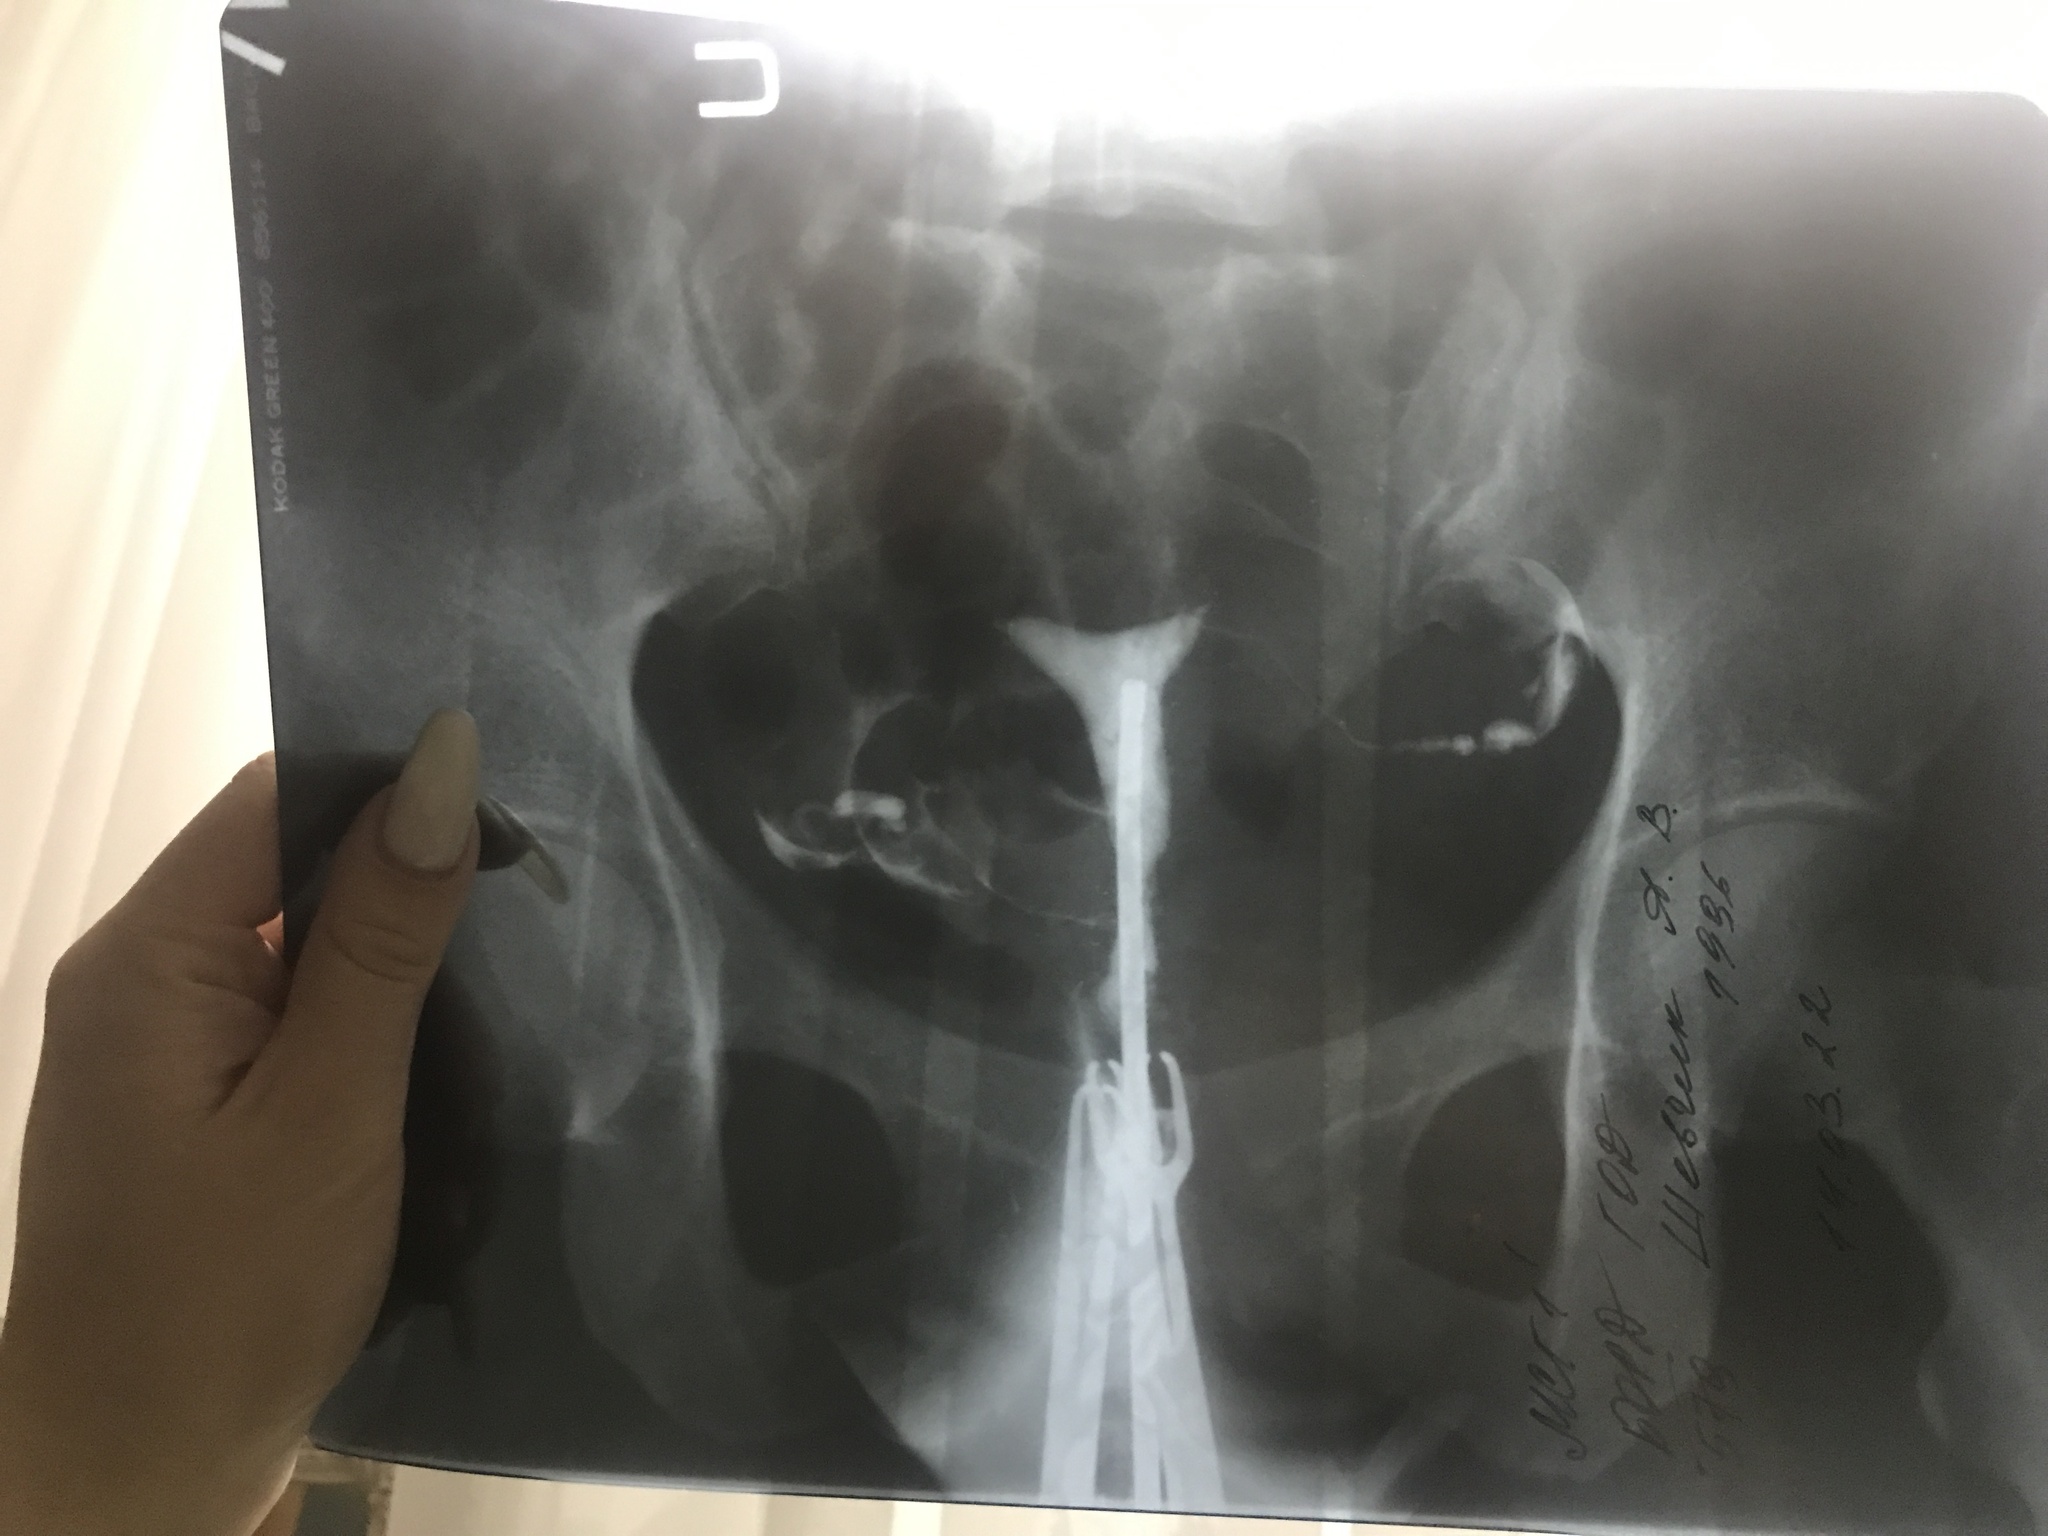

4. Гистеросальпингография. Этот пункт применим скорее для других заболеваний в этой рубрике, либо же в рамках обследования при жалобах на бесплодие